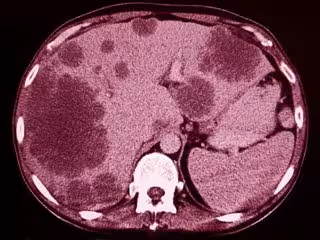

Metastasis

GETTY IMAGES/ISTOCKPHOTO / SEMNIC